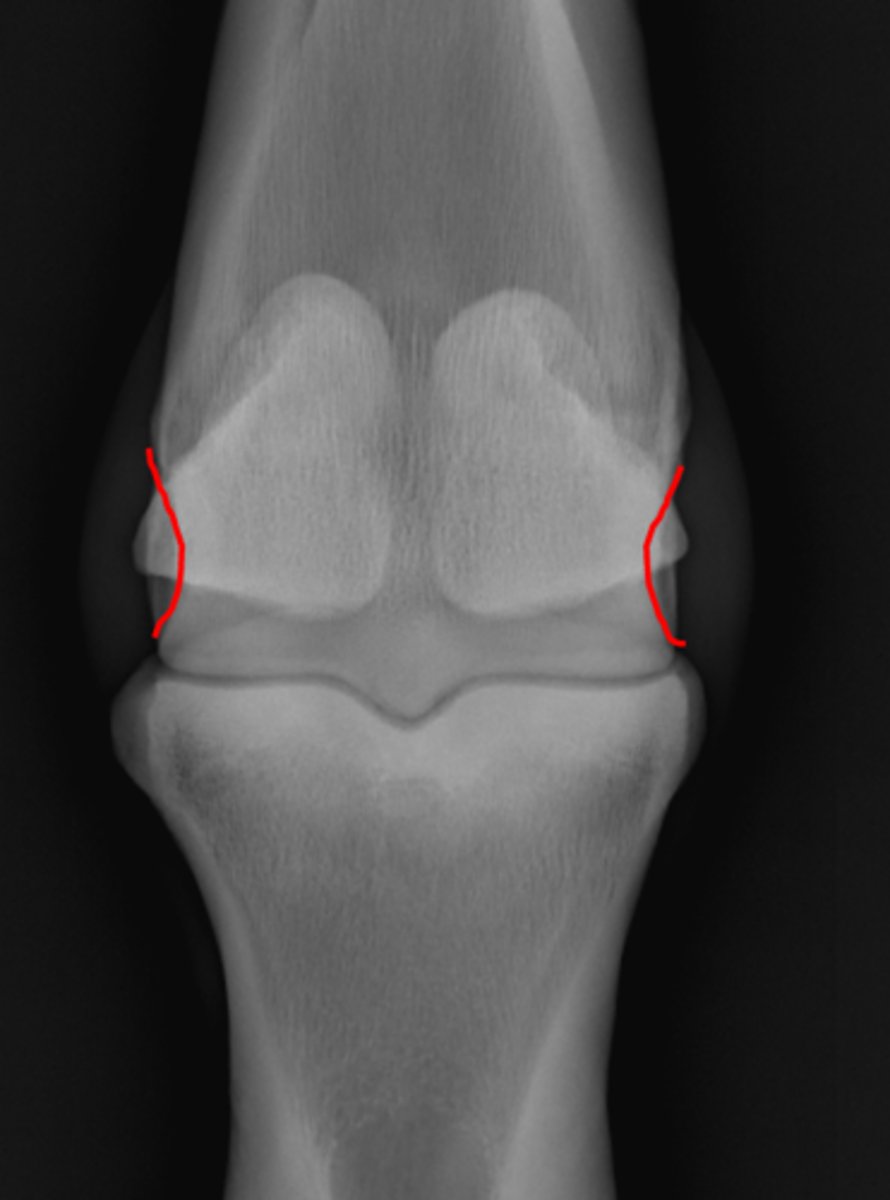

Fetlock joint, DP

ID joint and view